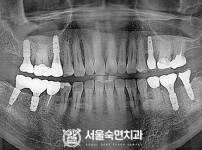

임플란트-전후사진3